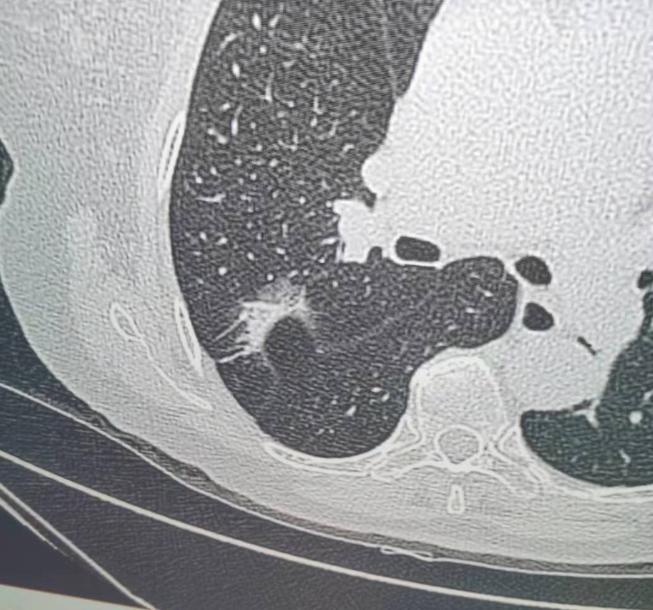

体检发现肺磨玻璃结节?别慌!大部分都是“好结节”!很多朋友体检做胸部CT,一看到